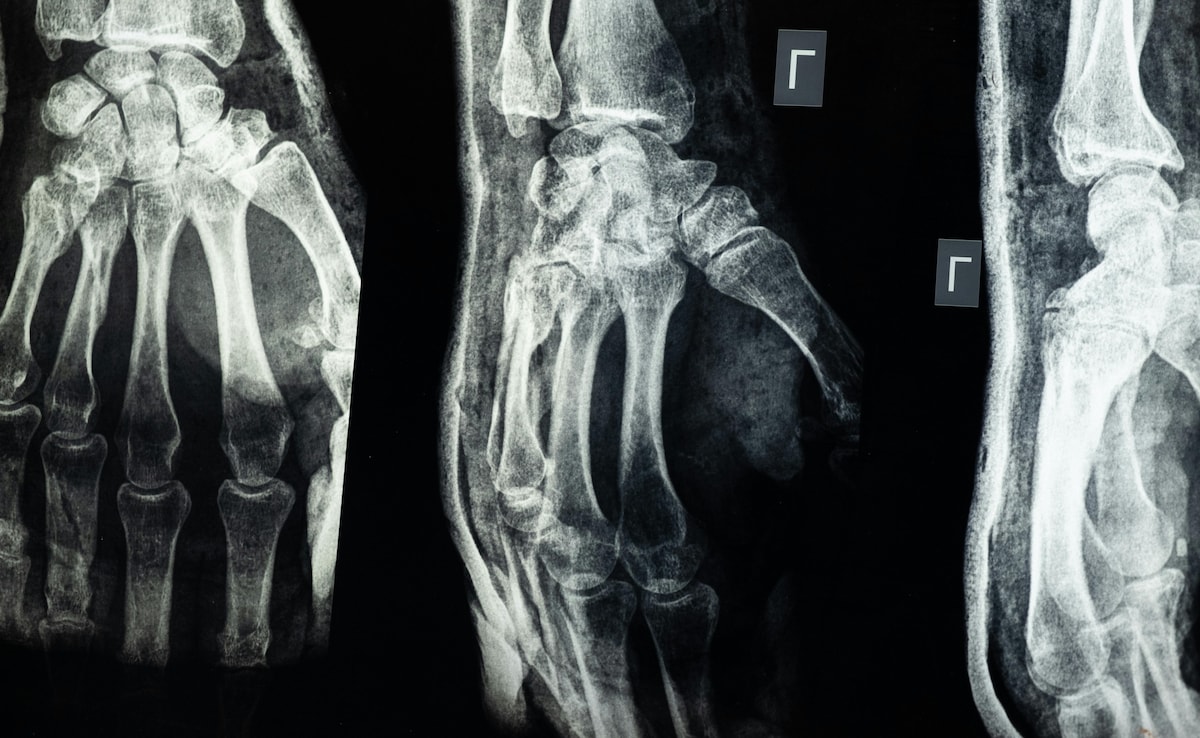

Chinese scientists have made a major medical breakthrough with the creation of a new bone glue called Bone-02, which has the potential to change the future of fracture treatment. This innovative adhesive can heal broken bones in as little as three minutes, forming a strong bond that allows the body to recover without the need for metal screws, plates, or follow-up surgeries. The most remarkable part of this development is that the glue is fully absorbed by the body over time, making the healing process more natural and reducing the risk of complications.

The innovation has already been tested in over 150 patients with various types of bone fractures. Results so far have been highly encouraging, showing rapid recovery, reduced pain, and no significant side effects. Patients who underwent procedures using Bone-02 were able to regain mobility faster and avoid the common complications associated with metal implants, such as infection, rejection, or the need for additional surgeries to remove hardware once the bone has healed.![]()